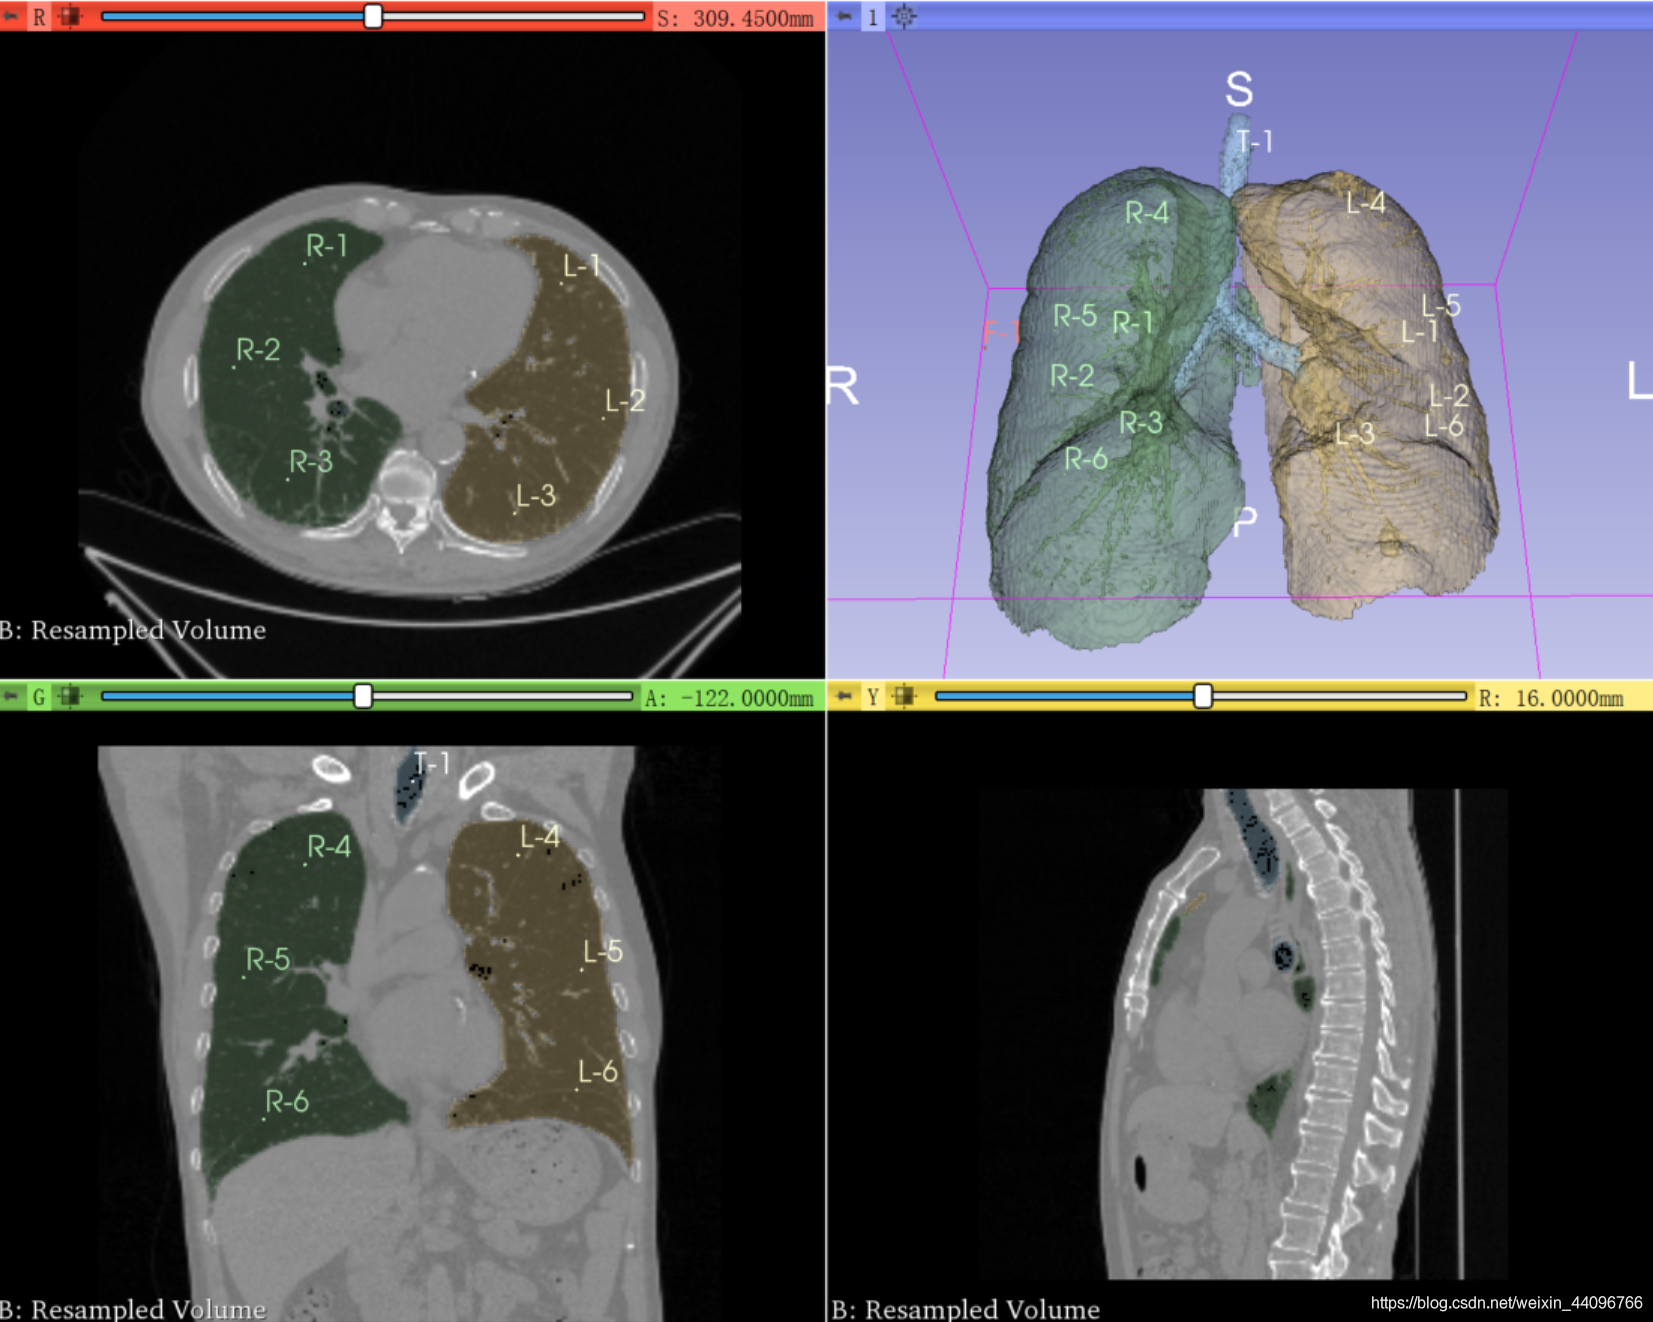

肺部分割

- 进入插件

- 点击start,根据提示在左、右肺、气管处标点后点击apply

分割出来的区域可以根据需要在Segment Editor中手动调整。

测量容积

- 进入插件

- show preview in 3D 查看3d效果